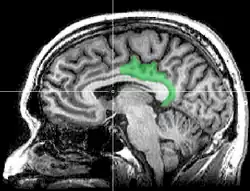

![]() Sagittal MRI slice with highlighting indicating location of the posterior cingulate | |